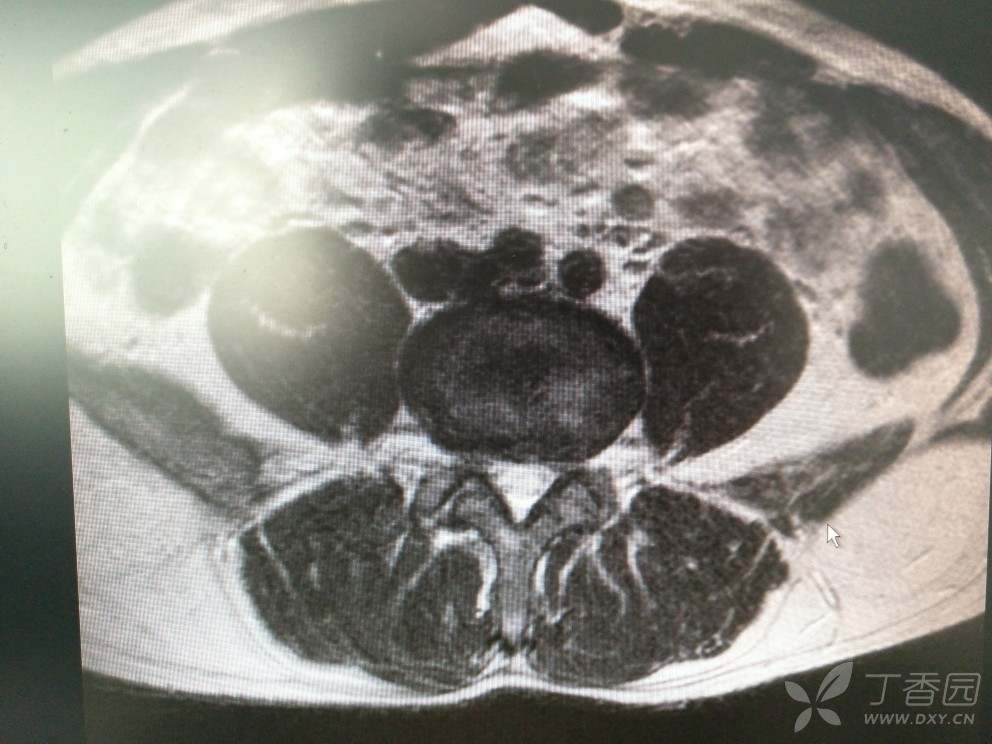

入院查MRI

我想问还是考虑L4/5 L5/S1椎间盘的变性引起的吗?